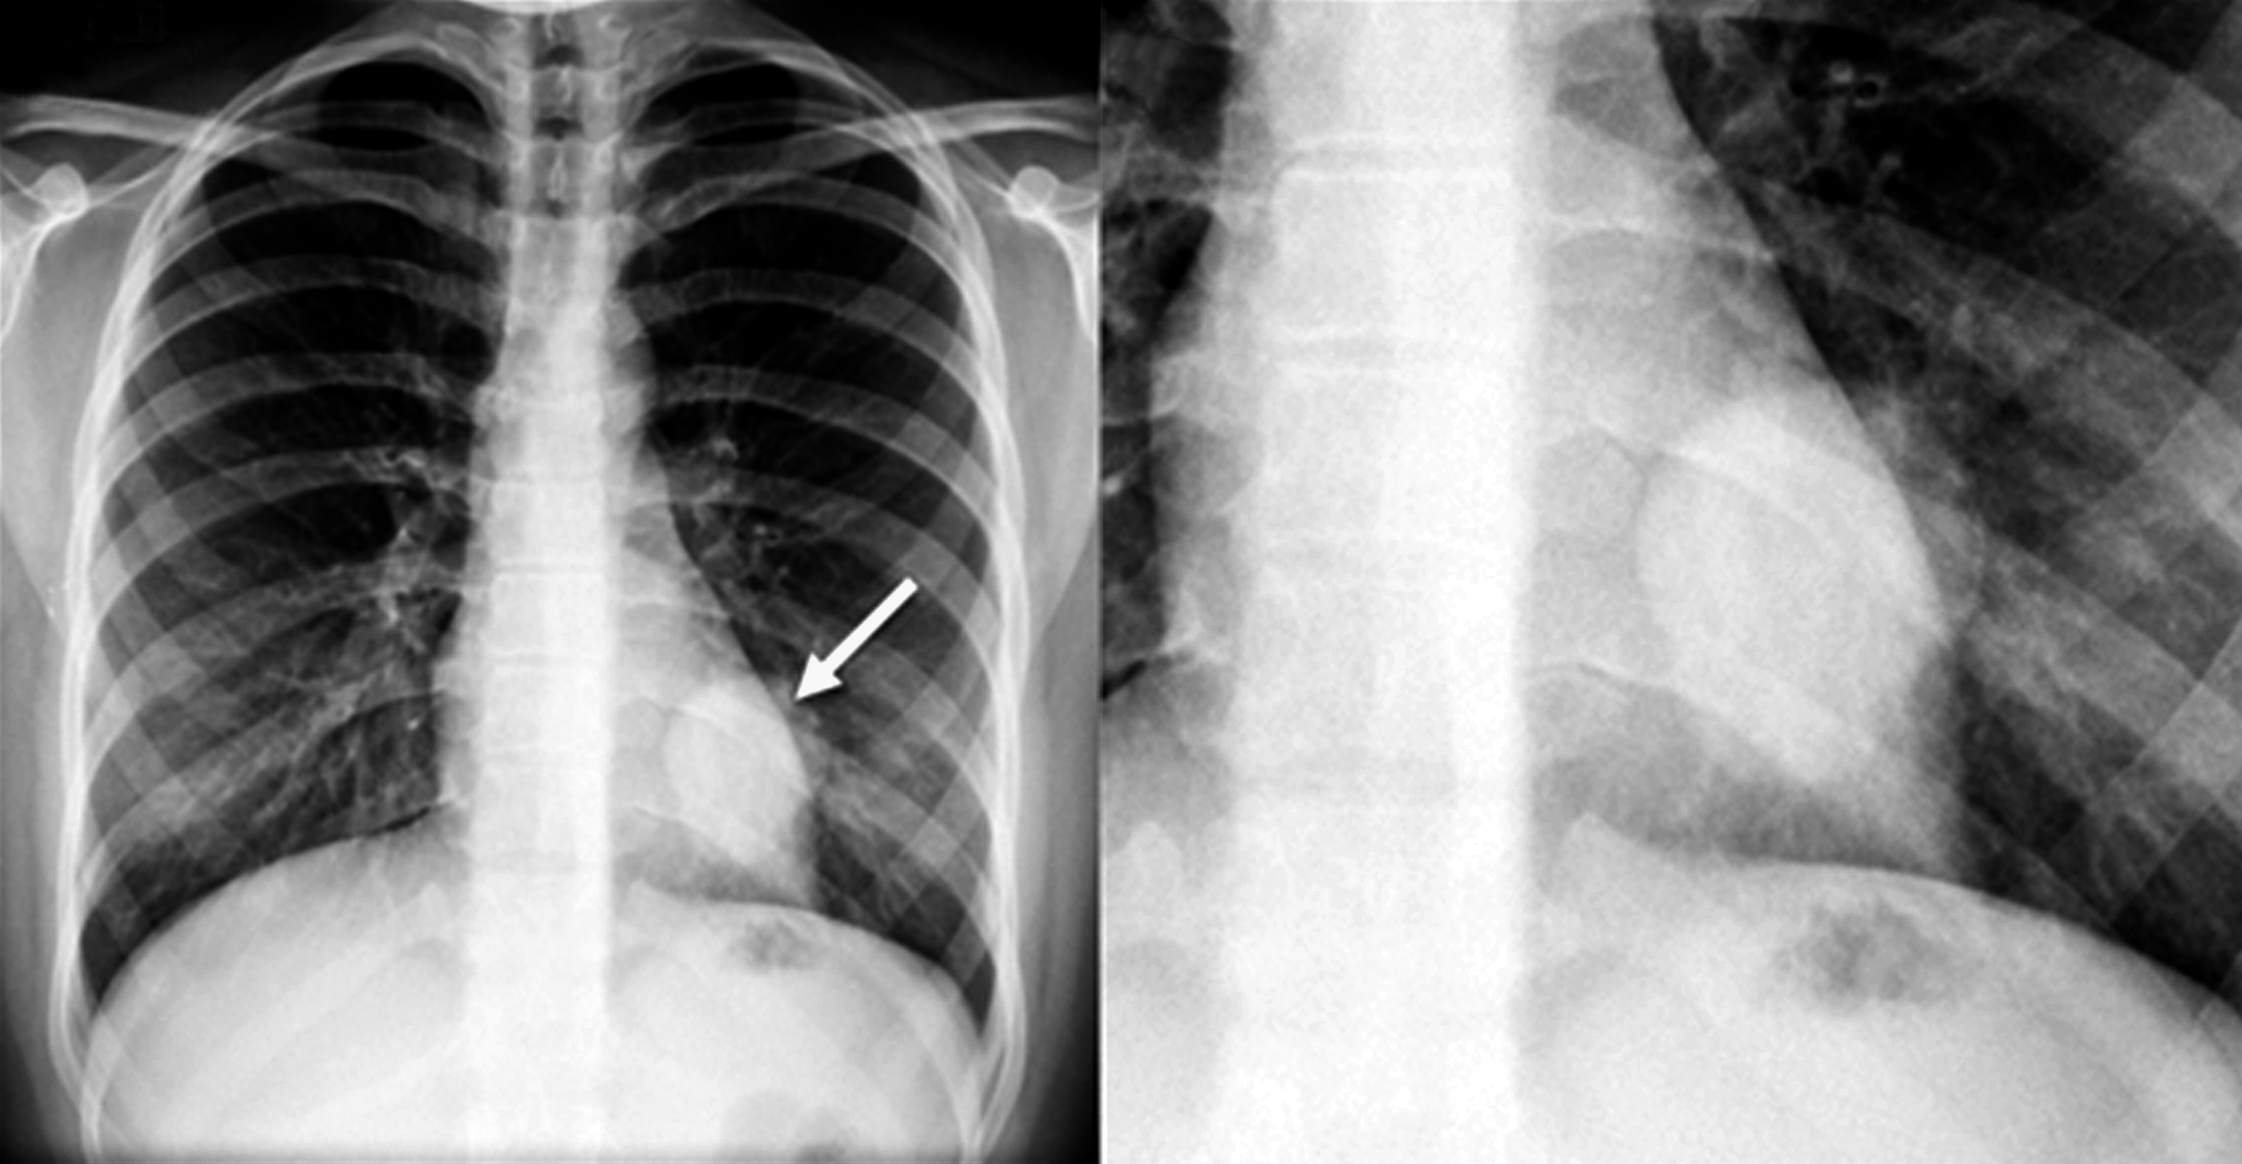

Se solicita radiografía de tórax de frente, en la cual se observa masa en tercio inferior de hemitórax izquierdo, retrocardíaca, redondeada, de bordes bien definidos, de aproximadamente 4 cm de diámetro. Resto del parénquima pulmonar y silueta cardiomediastínica sin alteraciones. (Figura 1)

Dados los hallazgos radiográficos se solicita tomografía computarizada de tórax. Se realizan adquisiciones sin y con medio de contraste intravenoso, en tiempo arterial y venoso. Se observa en el segmento apical del lóbulo inferior izquierdo una imagen sólida, redondeada, de bordes lisos y bien definidos, de 42 mm de diámetro, con pequeña calcificación en el sector inferior y realce homogéneo con el medio de contraste. No se observan otras alteraciones de la densidad del parénquima pulmonar, no hay derrame pleural, pericárdico, adenomegalias hiliomediastinales ni axilares. (Figura 2)

Figura 1

Radiografía de tórax, proyección PA (a) y aumento del sector de interés (b). Se observa masa retrocardíaca en hemitórax izquierdo (flecha).

Figura 2

TC con ventana de pulmón (a) donde se observa masa en hemitórax izquierdo rodeada de parénquima pulmonar sano. TC sin contraste intravenoso (b), en tiempo arterial (c) y en tiempo venoso (d) donde se observa el realce homogéneo.